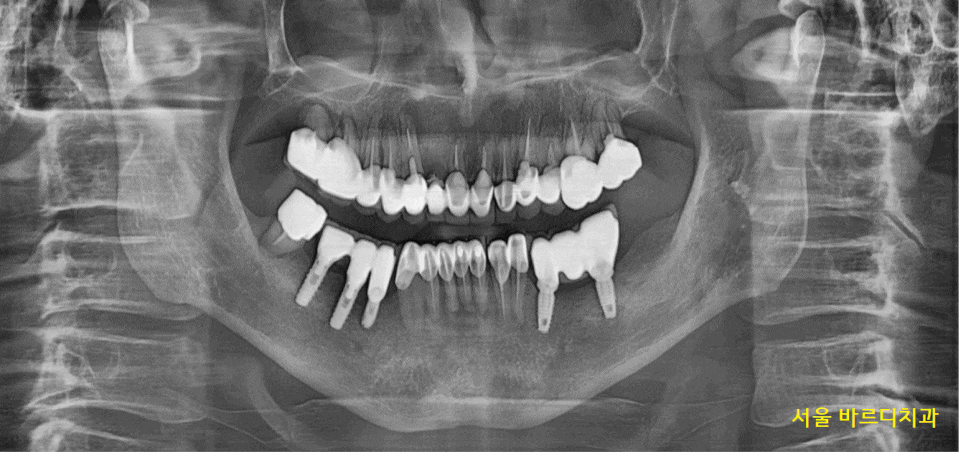

23.06.07

명일동 치과 방문해 주신

환자분과의 첫 만남 때의 사진입니다.

전반적으로 치료받으신 이가 많으시네요~